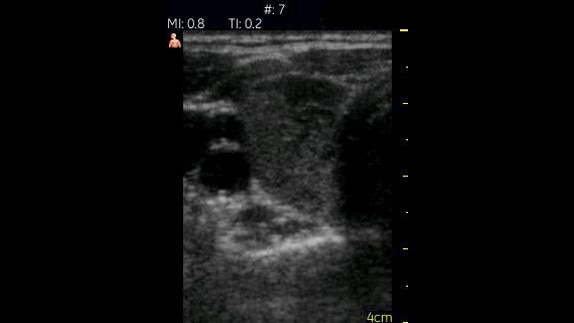

Hepatorenal Space